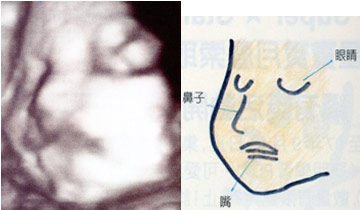

怀孕26周

怀孕26周

胎儿的手正好放在头上,似乎正在思考着事情。

怀孕27周

怀孕27周

胎儿的脑容量已经明显增大啰!

怀孕28周

怀孕28周

这张超音波照的胎儿,鼻子看起来还蛮高的唷!